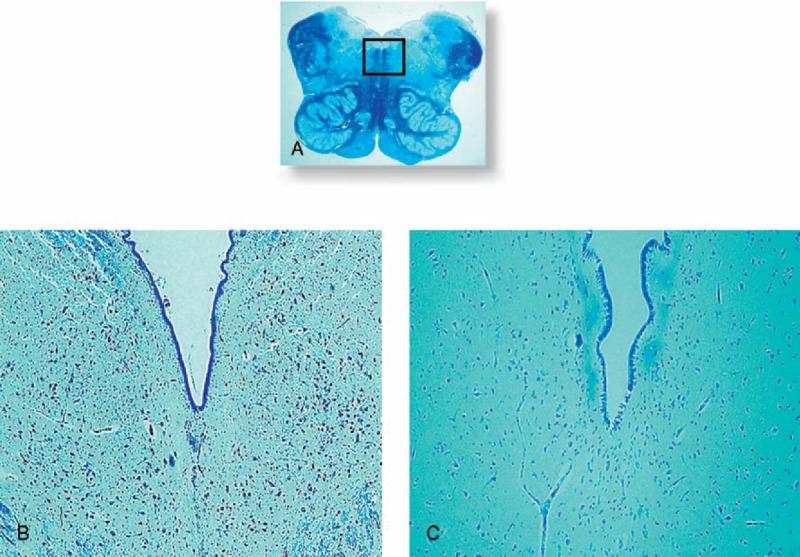

The inferior colliculus is a mesencephalic structure endowed with serotonergic fibers that plays an important role in the processing of acoustic information. The implication of the neuromodulator serotonin also in the aetiology of sudden unexplained fetal and infant death syndromes and the demonstration in these pathologies of developmental alterations of the superior olivary complex (SOC), a group of pontine nuclei likewise involved in hearing, prompted us to investigate whether the inferior colliculus may somehow contribute to the pathogenetic mechanism of unexplained perinatal death. Therefore, we performed in a wide set of fetuses and infants, aged from 33 gestational weeks to 7 postnatal months and died of both known and unknown cause, an in-depth anatomopathological analysis of the brainstem, particularly of the midbrain. Peculiar neuroanatomical and functional abnormalities of the inferior colliculus, such as hypoplasia/structural disarrangement and immunonegativity or poor positivity of serotonin, were exclusively found in sudden death victims, and not in controls. In addition, these alterations were frequently related to dysgenesis of connected structures, precisely the raphé nuclei and the superior olivary complex, and to nicotine absorption in pregnancy. We propose, on the basis of these results, the involvement of the inferior colliculus in more important functions than those related to hearing, as breathing and, more extensively, all the vital activities, and then in pathological conditions underlying a sudden death in vulnerable periods of the autonomic nervous system development, particularly associated to harmful risk factors as cigarette smoking.

下丘是一种中脑结构,具有5-羟色胺能纤维,在听觉信息处理中起重要作用。神经调质5-羟色胺在不明原因的胎儿和婴儿猝死综合征的病因学中的作用,以及在这些病理情况下上橄榄复合体(SOC)发育改变的证明,上橄榄复合体是一组同样参与听觉的脑桥核,促使我们研究下丘是否可能以某种方式促成不明原因围产期死亡的发病机制。因此,我们对大量胎龄从33周妊娠到出生后7个月、死于已知和未知原因的胎儿和婴儿进行了脑干,特别是中脑的深入解剖病理学分析。在下丘中发现了特殊的神经解剖学和功能异常,如下丘发育不全/结构紊乱以及5-羟色胺免疫阴性或弱阳性,这些仅在猝死受害者中发现,而在对照组中未发现。此外,这些改变经常与相连结构,即中缝核和上橄榄复合体的发育异常以及孕期尼古丁吸收有关。基于这些结果,我们提出下丘参与了比与听觉相关的功能更重要的功能,如呼吸以及更广泛的所有生命活动,进而参与自主神经系统发育脆弱期猝死的病理状况,特别是与吸烟等有害危险因素相关的情况。